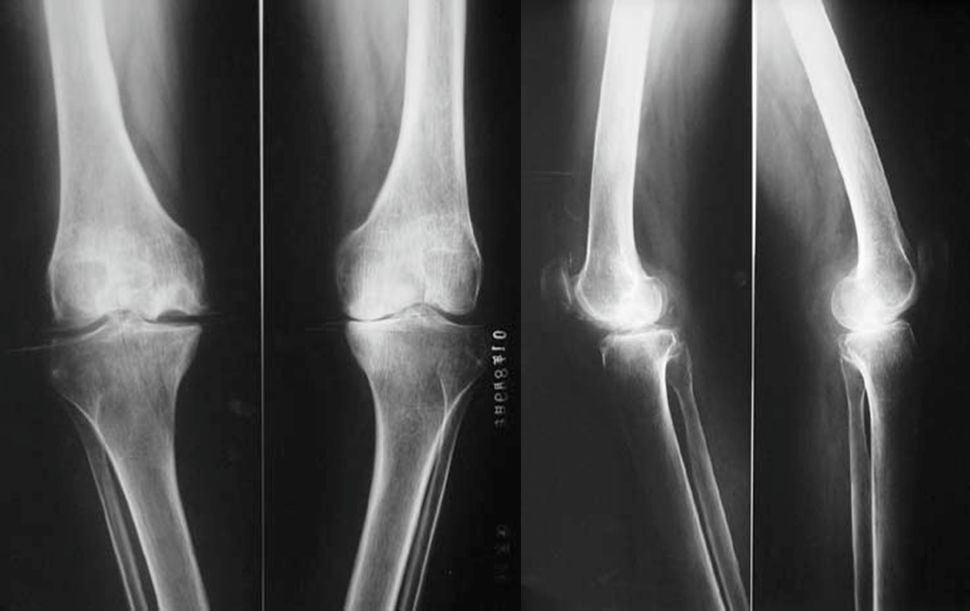

2、X线片(站立或负重位)示关节间隙变窄、软骨下骨硬化、和(或)囊性变、关节缘骨赘形成。

1、关节间隙变窄:成人膝关节间隙为4mm,小于3mm即为关节间隙狭窄,60岁以上的老人膝关节间隙为3mm,小于2mm为关节间隙狭窄。

2、软骨下骨板硬化:软骨下骨板致密、硬化,负重软骨下骨质内可见囊性改变。

3、骨赘形成。

软骨下骨板硬化